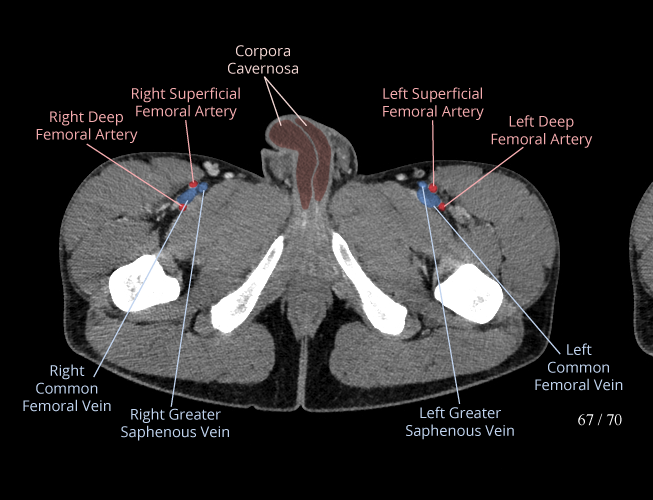

Body

Covers abdominal CT anatomy.

Pelvis

Covers pelvic MRI anatomy.